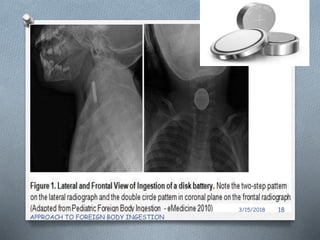

2.Neck /Chest/Abdominal Radiography

O Initial Investigation of choice

O Most ingested foreign bodies are radiopaque

(60%)

Determines :

O Presence

O Type

O location of the foreign body.

O Identifying possible complications

Removed immediately:

O Batteries in esophagus

O Batteries remaining in the stomach (> 48 h )

O Asymptomatic Disk batteries and

cylindrical batteries in stomach : upto 48

Hrs.

• #19 nce a disc battery moves past the esophagus and into stomach, systemic absorption is rare

• #22 alkaline caustic material causing mucosal ulceration,mercury poisoning, lithium absorption